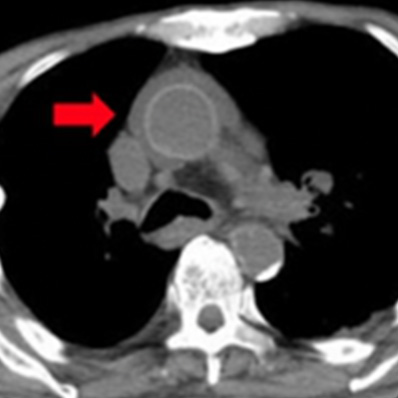

急性大動脈解離

(StanfordA型)